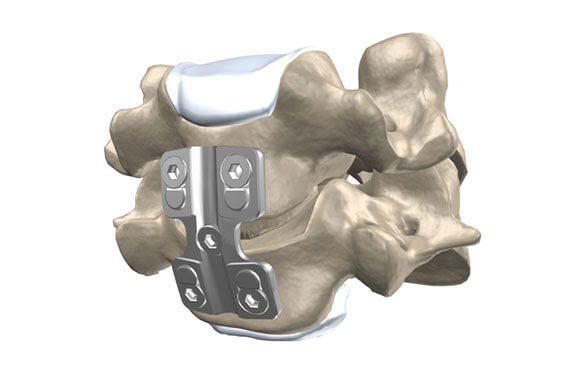

Prótese de disco

HÉRNIA DE DISCO CERVICAL

Cervical